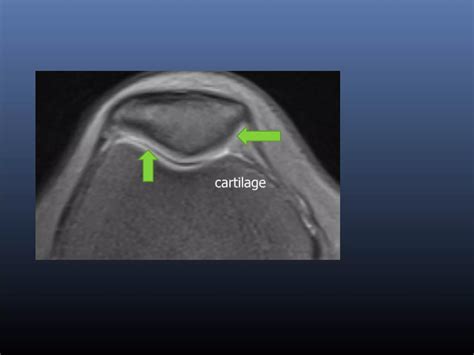

The Surprising Answer To Does Cartilage Regenerate In Humans

Adult Humans Can Regenerate Cartilage: Study | The Scientist Magazine®

Humans Have Ability to Regrow Damaged Cartilage, Study Reveals | Sci.News